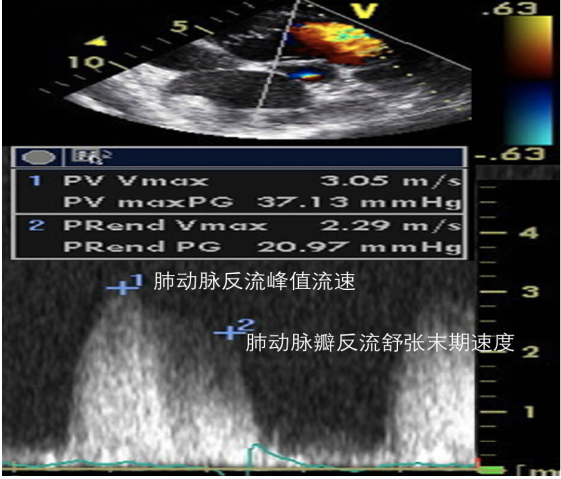

(3)肺动脉压:可以通过三尖瓣反流速度来评估图34,根据改良伯努利方程和估测的右房压来获得。其计算公式为:

肺动脉收缩压=4×(三尖瓣反流峰值速度2+右房压

肺动脉舒张压=4×(肺动脉瓣反流舒张末期速度)2+右房压

肺动脉平均压=4×(三尖瓣反流峰值速度)2

图片

图34. PA的测算